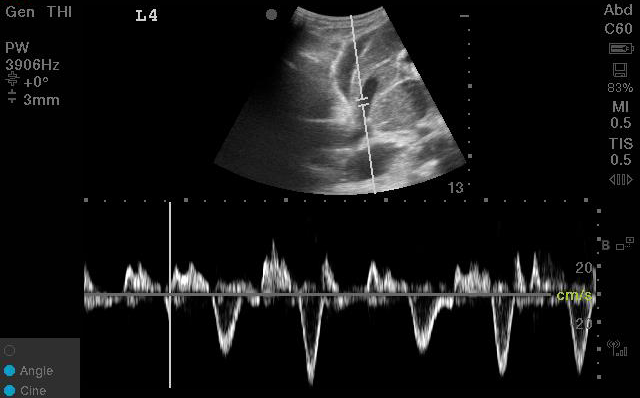

A quick #VEXUS thread 🧡-

3 reasons why the portal vein is the most useful single venous doppler waveform πŸ₯‡

(if you're only going to do ONE site to look for venous congestion, this is probably the most useful one!) 1. It's easy to obtain

Unlike the intra-renal veins, which can be elusive even to the most experienced scanners, the portal vein is usually easily identifiable.

From a right-sided coronal plane in the mid-axillary line, with your liver and kidney in view, the move is typically to fan or slide your probe in the anterior-posterior plane.

You should see a nice vertically-aligned segment of the portal vein pop into view; easily recognized by its bright hyperechoic borders and hepatopetal blood flow (which will look RED on colour doppler).